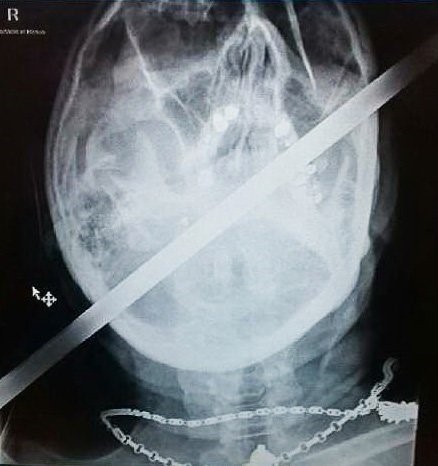

120-сантиметров метален прът пробива главата на моторист, полетял в канавка

Моторист оцеля по чудо след ужасна катастрофа, при която главата му е пронизана от 120-сантиметров метален прът, съобщава Sun.

Опитният мотоциклетист Пол от Скънторп, Линкс карал с приятели от местния мото-клуб,когато загубва контрол и излита в канавка. Там огромен метален кол се забива в главата му.

Медицински хеликоптер го откарва в болница, но не е опериран веднага, защото лекарите са изчакали жена му и двете му деца, за да го видят. Те смятали, че той няма почти никакъв шанс да бъде спасен и семейството му трябва да се сбогува с него.

Какво било обаче учудването им, когато той се възстановил след четиричасовата операция и дори го изписали след 2 дни!